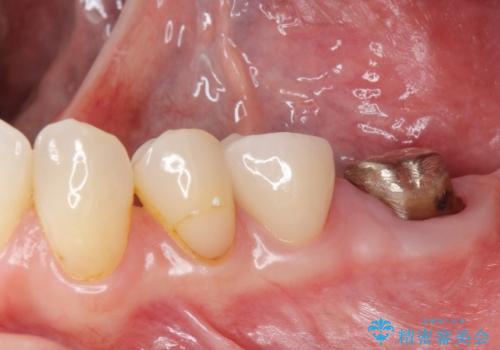

- ジルコニアクラウン・仮歯 12.1万円費用は治療当時の料金となります